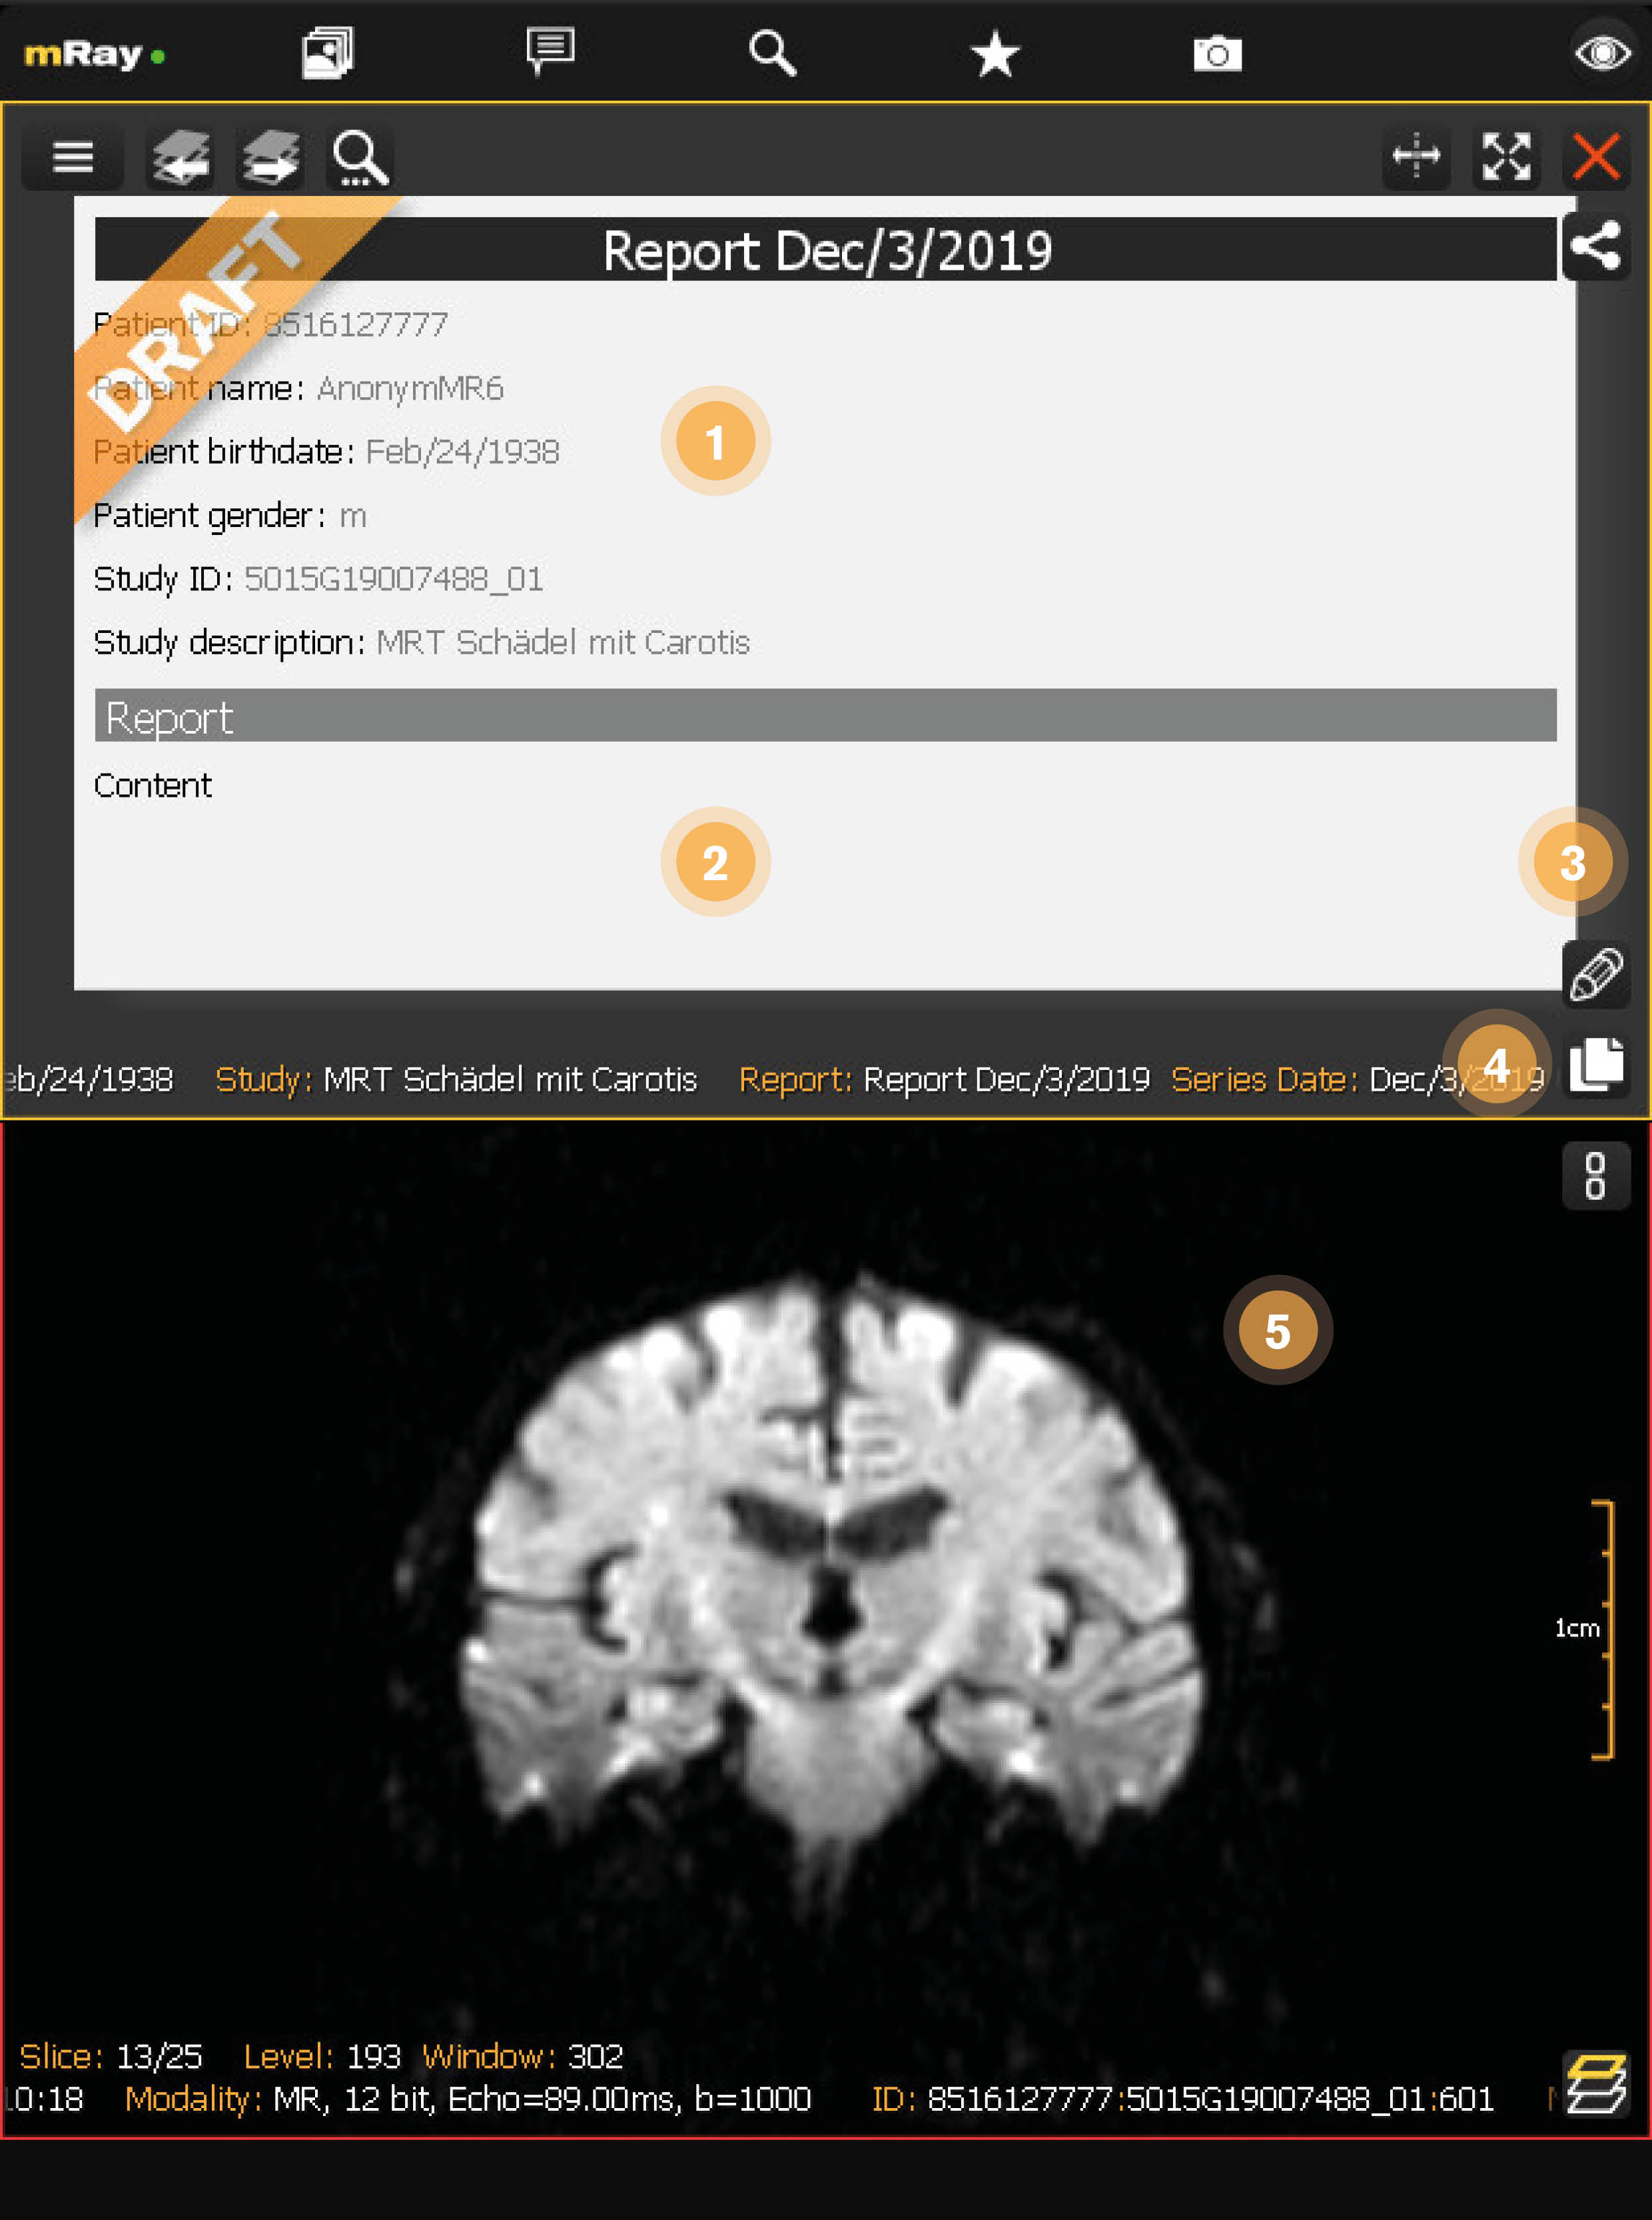

12.4. Draft reading view

When you reopen a draft from the inbox you can see the current draft state. You can always open this view even for locked drafts. When the report is locked by another user a closed lock is displayed.

-

Draft summary: A summary of the information in this draft.

-

Draft content: The text that has been added to this draft.

-

Edit draft: Edit this draft and open the Draft editing view

-

Copy content: Puts the content of this draft into your clipboard.

-

Associated study: Displays the study that is associated with this report.